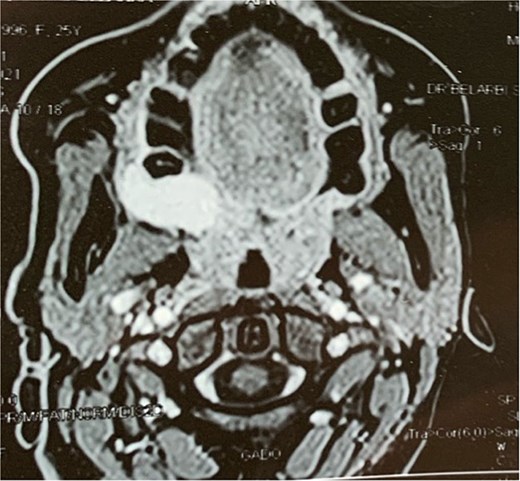

A facial CT scan shows a lesional process occupying the left infratemporal space, which is oval in shape, well-defined, and spontaneously isodense, with a calcified area and fine serpiginous vascular structures. It demonstrates heterogeneous enhancement after contrast injection (Fig. 5).

Facial MRI revealed a heterogenous soft tissue lesion in the infratemporal fossa measuring 47 × 51 × 53 mm, with imaging characteristics suggestive of a schwannoma of the third branch of the left trigeminal nerve.